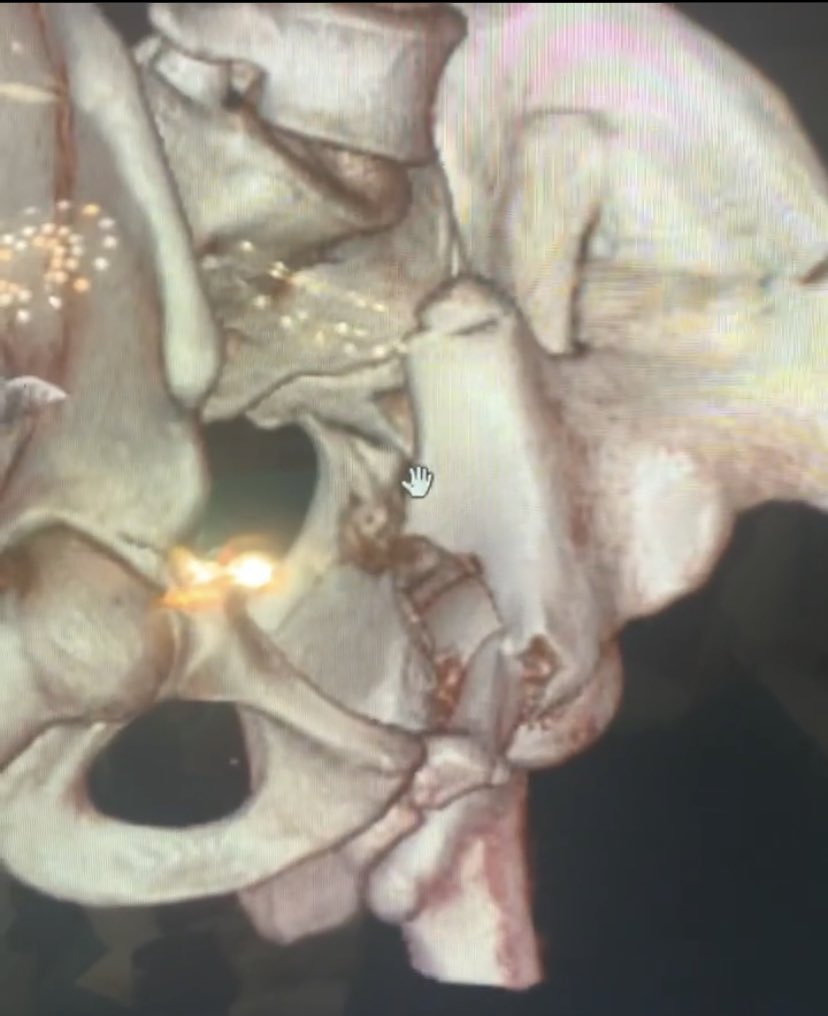

47 years old male patient, neglected (3 mounths) multilevel thoracolumbar junction spine fracture (L1, T12 and endplate of T11). there is monosegmental pure osseous failure of the posterior tension band in T12. this also called "Chance" fractures. #spinesurgery #spine